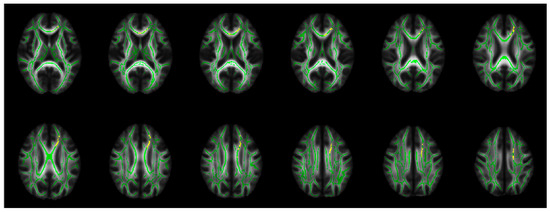

| PBD Compared to HC | |

|---|---|

| Findings | WM Tracts |

| Decreased FA (ptfce-FWE < 0.012 *) | Left parietal and occipital WM |

| Increased MD (ptfce-FWE < 0.012 *) | Left Fmin, gCC, bCC, ACR, SCR, and inferior frontal WM |

| Increased RD (ptfce-FWE < 0.008 **) | Bilateral orbitofrontal cortex WM, Fmin, gCC, bCC, ACR, SCR, PCR, anterior cingulum, inferior frontal WM, bottom part of the superior parietal lobule WM, posterior part of the superior longitudinal fasciculus, and posterior cingulum The left posterior part of the inferior fronto-occipital fasciculus and ILF, posterior thalamic radiation, optic radiation, lingual gyrus WM, splenium of the CC, forceps major, and the temporal part of the IFL |

| PBD Compared to NPBD | |

| Decreased FA (ptfce-FWE < 0.014 *) | Left parietal and occipital WM |

| Increased RD (ptfce-FWE < 0.014 *) | Left Fmin, gCC, bCC, and ACR |